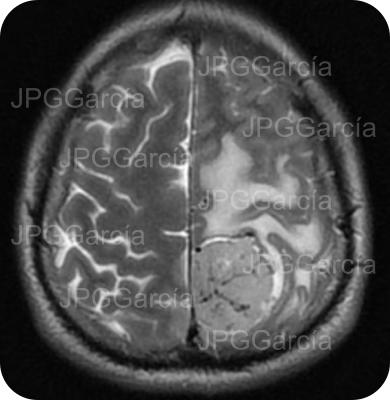

Resonancia magnética de cráneo en secuencias T1 y T2 que muestran una lesión ocupante de espacio de localización fronto temporal izquierda que ejerce efecto de masa aunado a edema perilesional